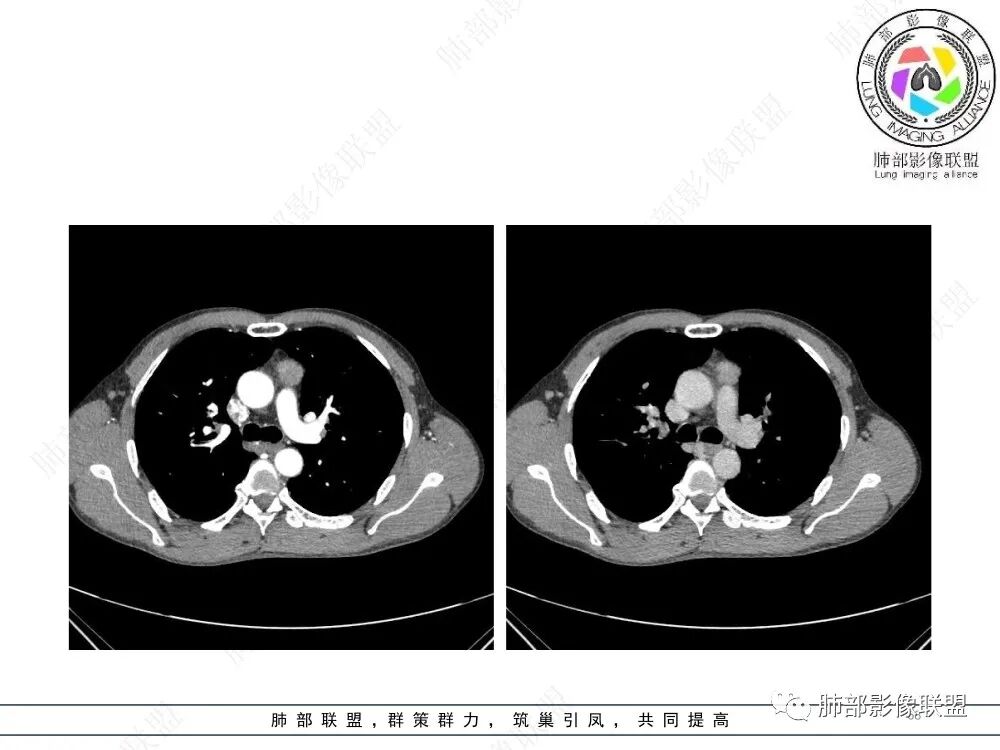

放射小白:男性47岁,前纵隔团块状占位,边界尚清,增强中度强化,内部疑似纤维分隔,常规考虑胸腺瘤可能(A/AB型),鉴别类癌、CD。

瑞欣:中年男性,检验未见明显异常,前纵隔软组织快影,边界清,可见明显强化,首先考虑胸腺瘤,鉴别淋巴瘤,畸胎瘤,生殖细胞瘤。

金豆:晨读:定位前纵隔,膨胀性生长,质地中等,边界清,有浅分叶,中等强化,似乎有裂隙低密度,常规胸腺瘤(B1)。

Yishion:晨读:纵隔占位,偏侧生长,边界清楚,有浅分叶,强化明显,其内似见纤维分隔,常规考虑胸腺瘤(AB型)。

蓝天白云:晨读:47岁男,前纵隔占位,边界清,有浅分叶,中等强化,胸腺瘤(B1)。

宇宙:前纵膈偏左类圆形肿块,边界清晰光整,与大血管脂肪间隙清,密度均匀,轻中度强化,考虑胸腺瘤,A型?鉴别胸腺癌。

玫:男,47岁,咳嗽,咳痰一年,前纵隔软组织密度肿块影,边界清晰,内密度均匀,增强扫描轻度强化,考虑胸腺瘤可能。

周太狼:中年男性,前上纵隔胸腺区软组织团块占位,边界清,增强中度强化,内密度较均匀,常规考虑胸腺瘤。

月亮圆了!:前纵隔包块,边界清,有分叶,密度不均,中等强化,考虑胸腺瘤。

衡妈🇨🇳:中年男性,前纵隔偏左侧实性占位,密度相对均匀,边缘分叶,周围脂肪结构略模糊,增强后动脉期不均匀强化,有低密度区,纤维分隔显示不清。考虑胸腺瘤B1 B2型。

朱伟超:中年男性,前纵膈偏离中线肿块,浅分叶,内有分隔,中等不均匀强化,常规胸腺瘤。

流心明智:男,47,咳嗽、咳痰1年余。胸部CT:前纵膈偏左类圆形肿块,瘤肺界面清晰光整,纵隔侧部分层面絮状影?平扫密度较均匀,增强后轻度强化,内可见宽带及线样低密度分隔。邻近左上肺受压凹陷。考虑胸腺肿瘤,AB型?胸腺Ca?鉴别淋巴瘤、N源性肿瘤、CD等。

2、影像特点:前纵隔偏左侧软组织影,密度相对均匀,未见明显包膜钙化及实质内钙化,局部边缘浅分叶,周围脂肪间隙密度增高、浑浊,未见侵犯大血管、未见纵隔内淋巴结转移、未见侵犯心包内结构、未见胸膜转移结节、未见肿块沿着纵隔胸膜蔓延,未见胸腔积液。增强后动脉期不均匀强化,未见明显纤维分隔。